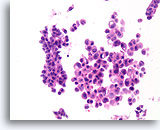

Ductaal carcinoom, Borst FNA, ThinPrep®.

Ductale cellen vormen een verscheidenheid aan losgekomen micropapillaire en holle clusters.

10X

Ductaal carcinoom, Borst FNA, ThinPrep®.

Ductale cellen vormen een verscheidenheid aan losgekomen micropapillaire en holle clusters.

10X

Ductaal carcinoom, Borst FNA, ThinPrep®.

Bij een sterkere vergroting kunnen de stratificatie van de ductale cellen, random polariteit, milde nucleaire atypie en afwezigheid van een duidelijke myoepitheliale populatie worden waargenomen.

60X

Ductaal carcinoom, Borst FNA, ThinPrep®.

Bij een sterkere vergroting kunnen de stratificatie van de ductale cellen, random polariteit, milde nucleaire atypie en afwezigheid van een duidelijke myoepitheliale populatie worden waargenomen.

60X

Ductaal carcinoom, Borst FNA, Celblok.

Een overeenkomstige weefselcoupe toont de micropapillaire (solide) en holle glandulaire groepen, met afzonderlijke cellen in de achtergrond.

10X

Ductaal carcinoom, Borst FNA, Celblok.

Een overeenkomstige weefselcoupe toont de micropapillaire (solide) en holle glandulaire groepen, met afzonderlijke cellen in de achtergrond.

10X

Ductaal carcinoom, Borst FNA, Celblok.

De weefselcoupe van een soortgelijk veld als het veld in afbeelding 70 wordt afgebeeld.

60X

Ductaal carcinoom, Borst FNA, Celblok.

De weefselcoupe van een soortgelijk veld als het veld in afbeelding 70 wordt afgebeeld.

60X